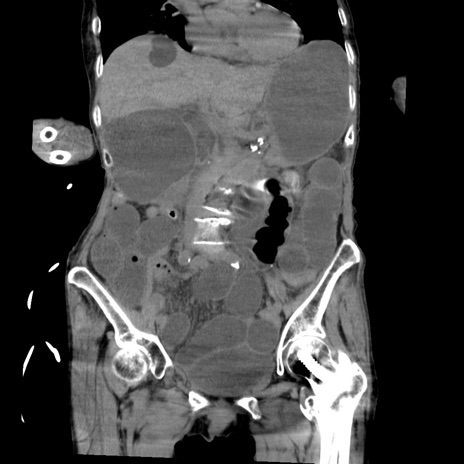

症例27(冠状断像)

【症例】80歳代女性

【主訴】嘔吐、腹痛

【現病歴】数時間前より嘔吐あり。心窩部痛出現し、徐々に右下腹痛あり。その後も数回嘔吐あり救急搬送となる。

【既往歴】左大腿骨頚部骨折手術

【身体所見】腹部は膨隆しているが軟らかく圧痛なし。腸雑音はやや亢進。

【データ】WBC 12000、CRP 19.05